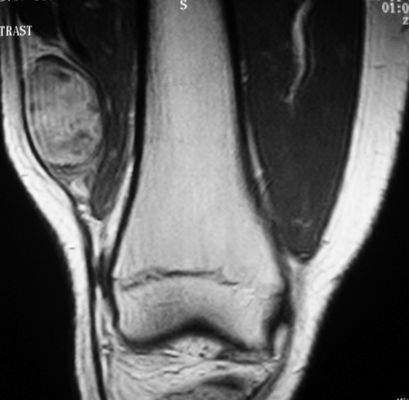

Саркома мягких тканей бедра на МРТ

Снимок МРТ коленного сустава